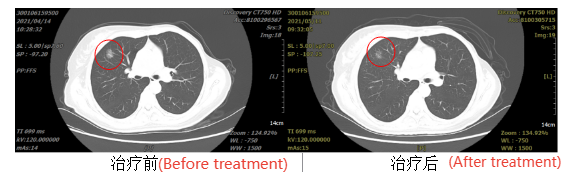

Patient, female, 55 years old, with right lung cancer, staged as cT1N0M0 (IA).